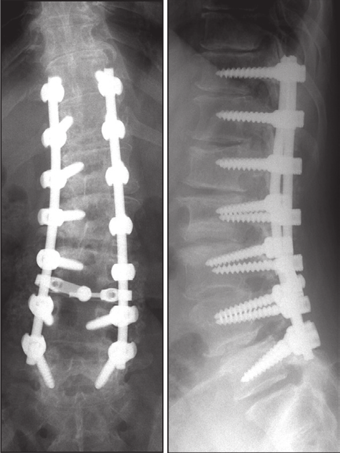

图5 脊柱远端融合节段越多,如包括L5-S1水平固定到骶骨或髂骨,发生交界性后凸的可能性越大

图6 长节段融合固定上固定椎(UIV)选择在胸10-12胸腰椎交界区是PJK的风险因素之一

图24 左:长节段固定至髂骨;右:长节段固定

图25 降低内固定硬度和减少融合区内固定数量